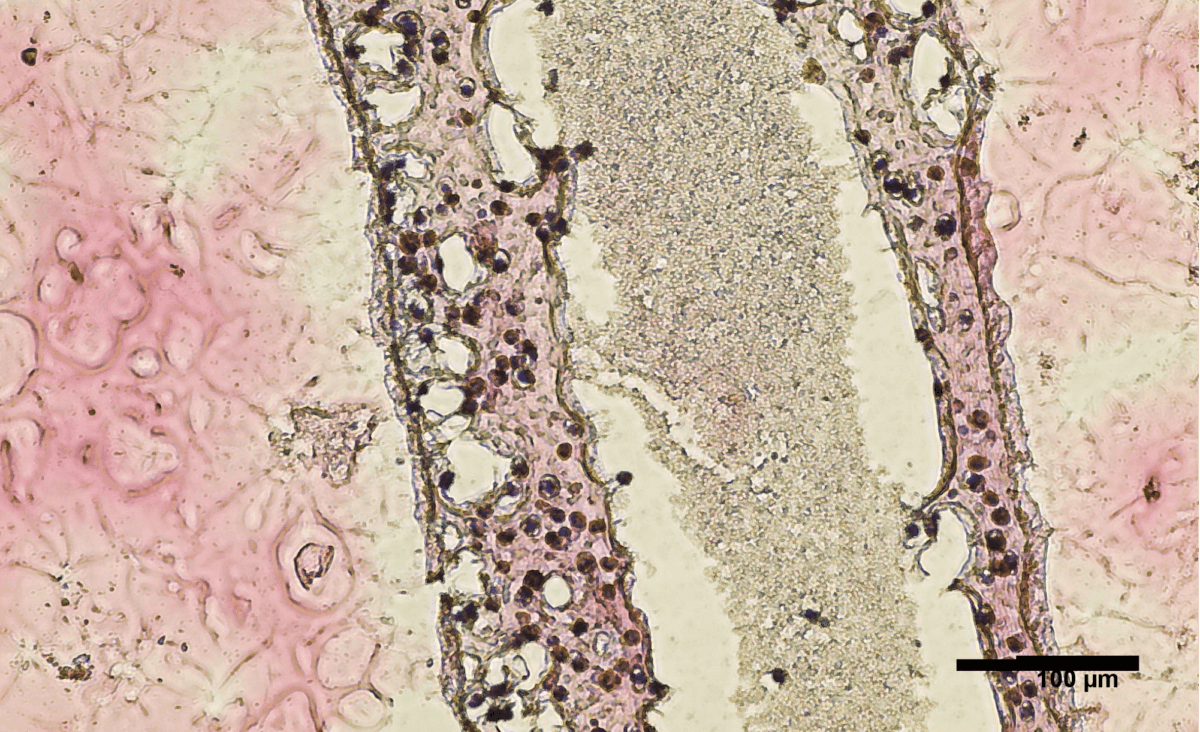

Cross section of human testicular cells 3D printed into a tubular structure. (Credit: University of British Columbia)

In the new study, researchers performed a biopsy to collect stem cells from an NOA patient’s testicles. Study authors then grew these cells and 3D printed them into a hollow tubular structure — resembling the seminiferous tubules.